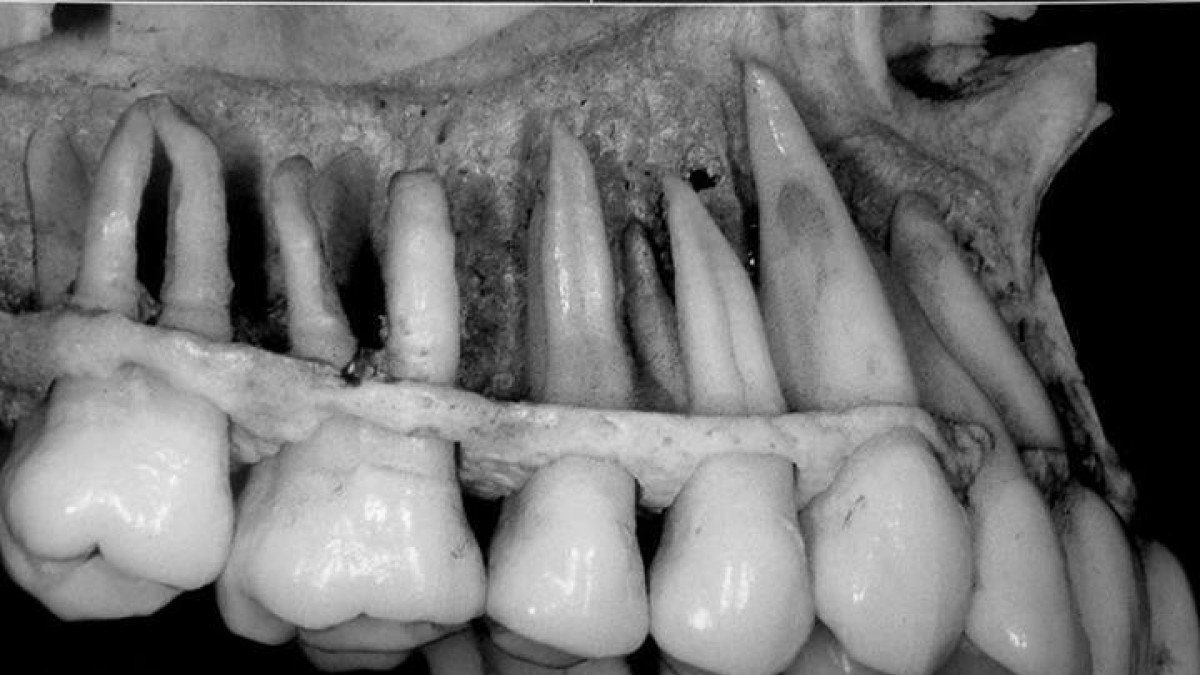

Gördükleriniz sadece buz dağının görünen kısmı! İşte dişlerle ilgili ilginç gerçekler:

- Dişlerinizin 3'te 2'si diş etinizin altında konumlanır.